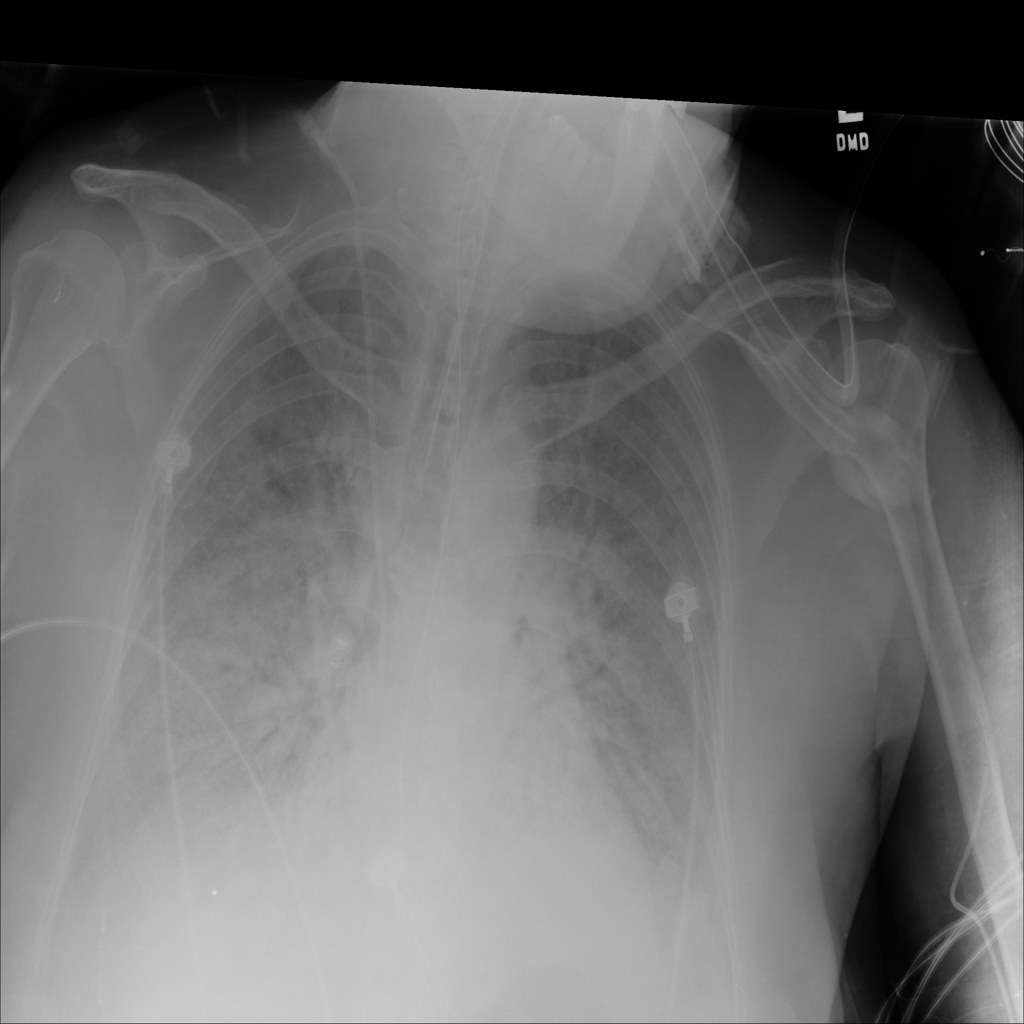

PAT-C1A7 · IMG-004Consolidation

PAT-C1A7 · IMG-004

PA